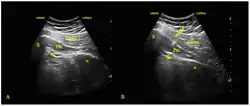

Diagnostic modalities such as EMG, x-rays, ultrasound, CT, MRI is mostly used to exclude other conditions.[29][30] For example, and MRI of the spine can rule out conditions like radiculopathy and spinal stenosis. MRI of the pelvis can rule out conditions like pelvic tumors.[29] MRI and ultrasound can be used to observe side-to-side differences, a common finding where the symptomatic side often exhibits increased piriformis size measured as increased thickness and cross-sectional area.[33][34][20] Specialized sequences and protocols of MRI can be used for sciatic nerve imaging, namely MRN (magnetic resonance neurography) and DTI (diffusion tensor imaging). MRN can assess changes in the path, thickness, and signal intensity of the sciatic nerve.[35] DTI uses the anisotropic diffusion of water to assess structural and functional properties of nerves.[36] Both MRN and DTI can localize nerve lesions, their extension, and their spatial distribution due to conditions such as entrapment.[37][38] MRN and DTI have also been used to visualize sciatic nerve lesions to diagnose of piriformis syndrome.[20][39][40][41] However, magnetic resonance neurography is considered "investigational/not medically necessary" by some insurance companies. Neurography can determine whether or not a patient has a split sciatic nerve or a split piriformis muscle – this may be important in getting a good result from injections or surgery.

Image-guided injections into the piriformis muscle can assist in the diagnosis.[29] Injections usually involve delivering anesthetic to the piriformis muscle to paralyze it.[20] In the event of a piriformis muscle spasm causing sciatic nerve compression, paralyzing the piriformis muscle will temporarily relieve the symptoms.[20] If successful, there should be a complete or near-complete relief of pain for 4–6 hours.[20][42] Needle guidance can be done with fluoroscopy, ultrasound, CT, or MRI.[30] Ultrasound is a popular choice due to its low cost, lack of radiation, and accessibility, but lacks the spatial resolution of CT/MRI.[43][44] While there is no gold standard test to diagnose piriformis syndrome,[2] in deep gluteal syndrome, the generalization of extra-spinal sciatica in the deep gluteal space, diagnostic blocks are considered the gold standard for differentiating alternate sources of pain.[45]

Injections are part of multi-modal therapy and can be therapeutic.[29][2] They may be used with conservative treatments like physical therapy or after the failure of conservative treatments. Injections deliver medication directly to the piriformis muscle through a needle. The needle is placed into the piriformis muscle with image guidance such as fluoroscopy, ultrasound, CT, or MRI.[2][30] Ultrasound is a popular choice due to a balance of accuracy, accessibility, lack of radiation exposure, and affordability.[29][2]